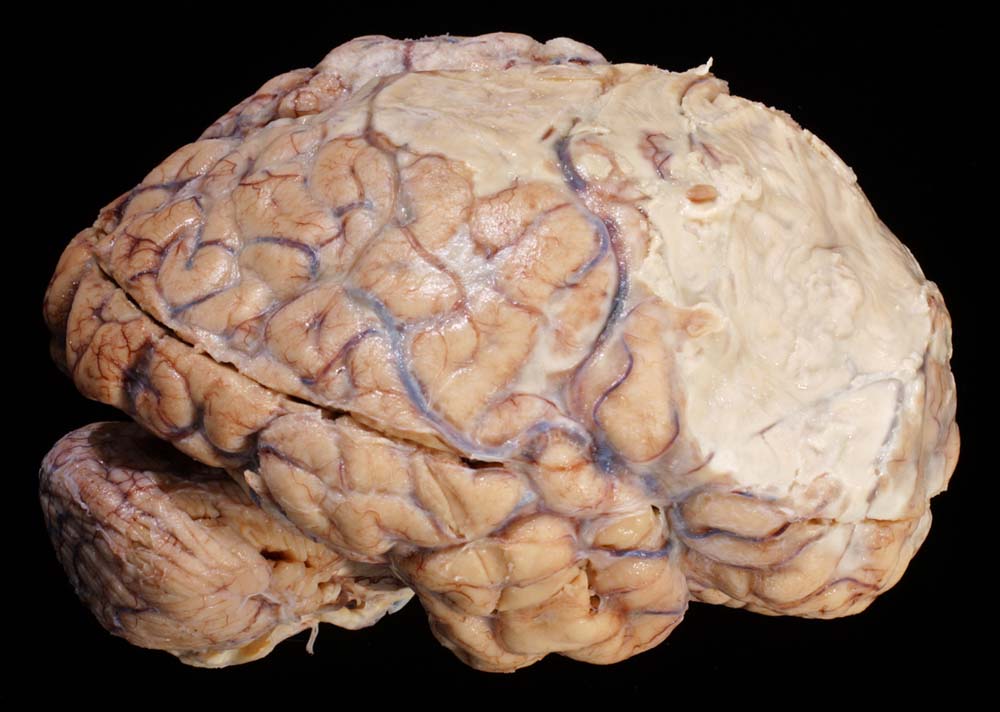

Der makroskopische Befund bei bakterieller Meningitis kann sehr diskret sein. Die meningealen Gefässe sind hyperämisch und die Hirnoberfläche wird von einem grüngelben Eiterbelag bedeckt (eher basal bei Hämophilus influenzae, eher über der Konvexität bei Pneumokokken=Haubenmeningitis). Histologisch ist der Subarachnoidalraum mit Eiter gefüllt. Bei weniger schweren Fällen finden sich die neutrophilen Granulozyten bevorzugt um die leptomeningealen Gefässe.

• Der verbreiterte Subarachnoidalraum ist mit Eiter und Ödemflüssigkeit ausgefüllt.